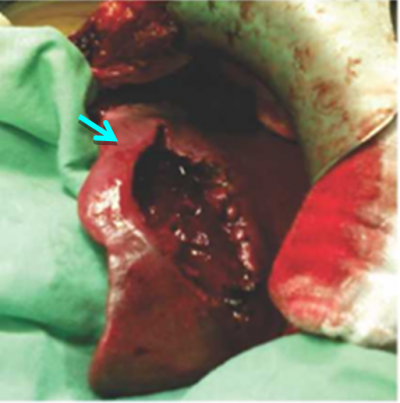

הטיפול בהמנגיומות הוא שמרני וכולל מעקב באחד מאמצעי ההדמיה. בהמנגיומות שגדלות או המנגיומות תסמיניות הגורמות לחץ על איברים או דימום, הטיפול בהן הינו כריתה כירורגית שלהן. בדרך כלל אפשר להסתפק באנוקלאציה (Enucleation) של ההמנגיומה ולעתים רחוקות יש צורך בכריתת כבד (תמונה 6.10-7.10).

במקרים נדירים ביותר של גידולים גדולים או כאלה הגורמים לסימפטומים, יש צורך בניתוח לכריתת השאת (תמונה 8.10).

| |

| תמונה 8.10: FNH משמאל מראה השאת בניתוח (חץ). מימין FNH לאחר הוצאתו מהכבד. למטה חתך מאקרוסקופי של הגוש. | |